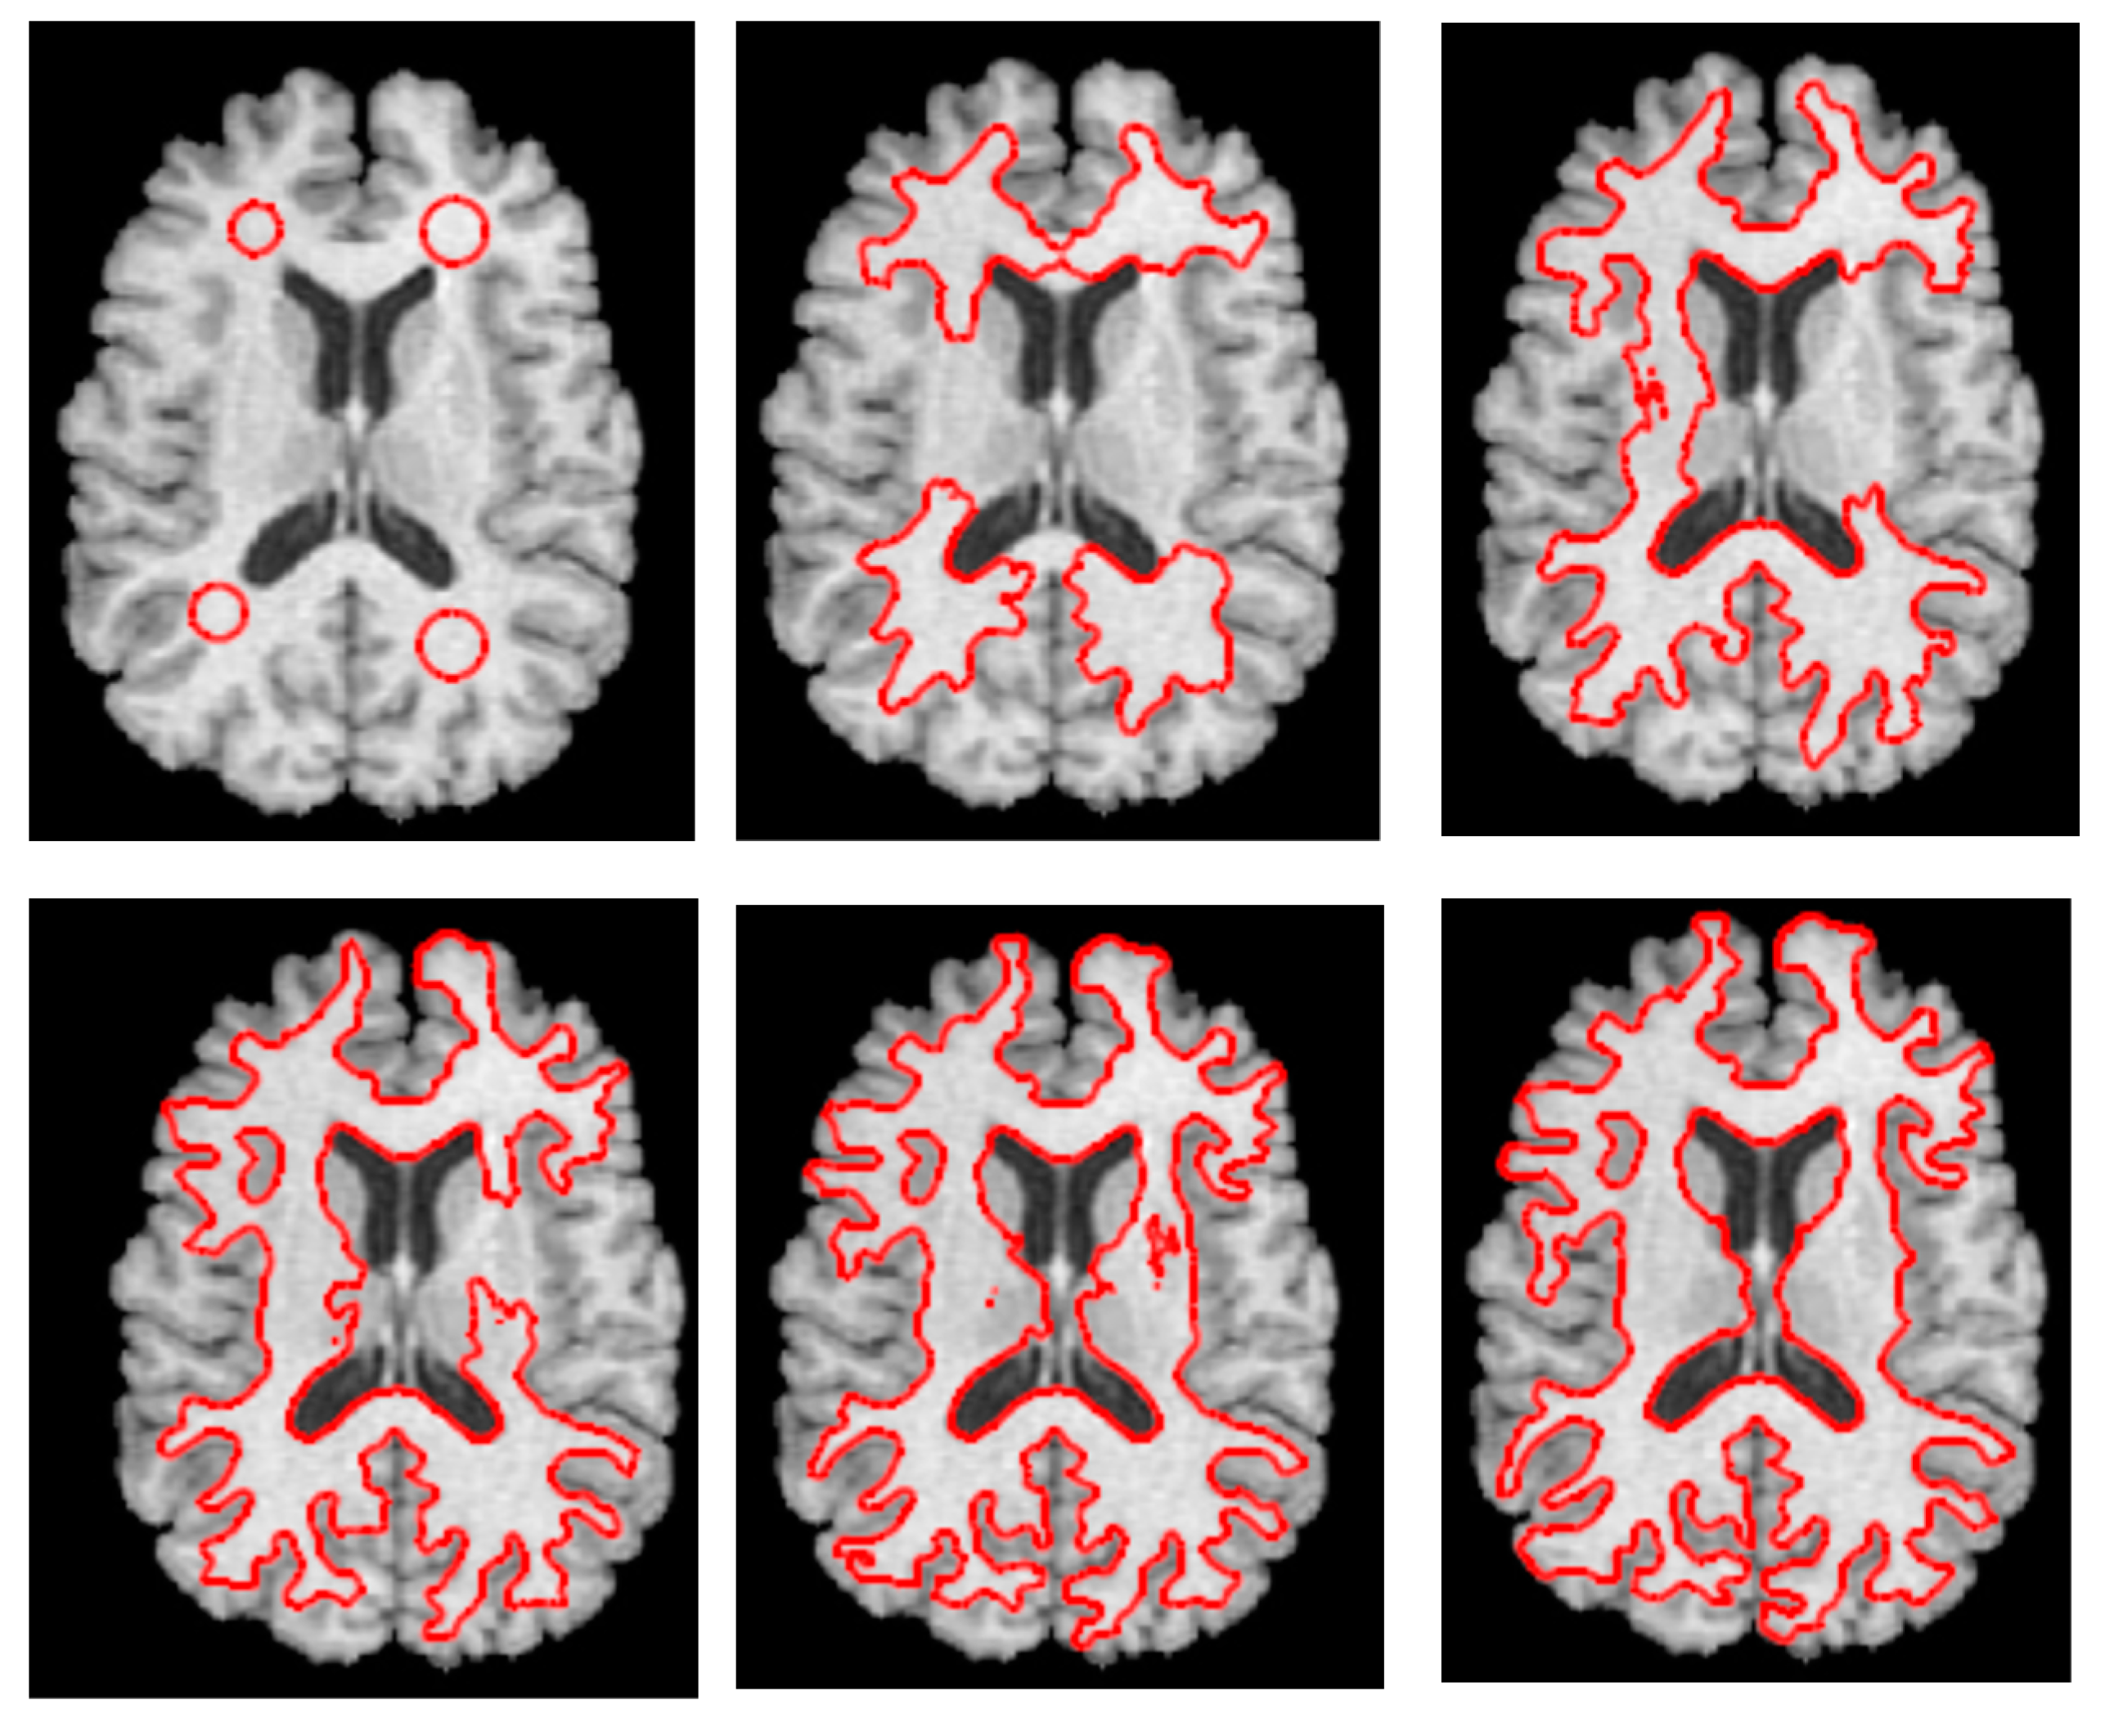

3.3. Step 3 Level Set Segmentation

3.2.2. Determine Initial Contour Points Using Quantum Dragonfly Algorithm